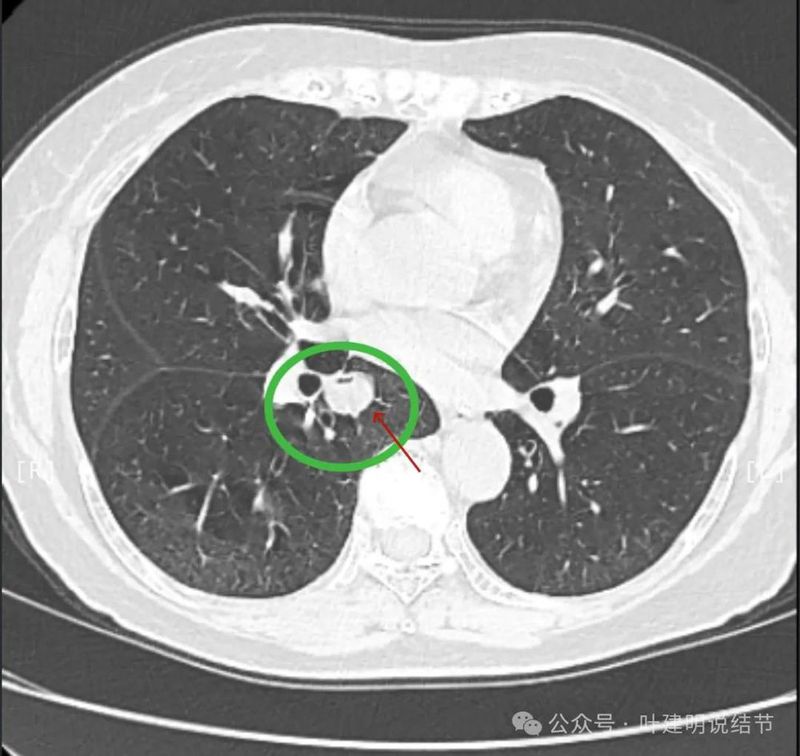

内部密度较为均匀,就位于肺门部。

边缘光滑,实性,有膨胀感。

与血管关系近。

边缘区域与下肺静脉间隙不太清楚。